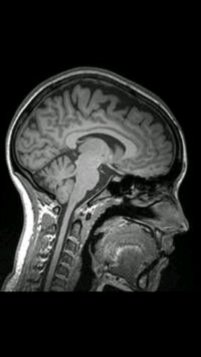

Over the past year and a half, I have been witness to the painfully relentless progress of a glioblastoma multiforme invading my brother’s brain. Utilizing every possible strategy one could employ in response to such an affliction, my brother has extended his original prognosis of a fourteen month survival duration to twenty-seven months. These last three months have seen his physical condition deteriorate more rapidly than ever before, and as I write, he is struggling just to breathe. The tumor in his brain is pressing against his left parietal lobe, severely affecting his ability to speak and it has virtually paralysed his entire body.